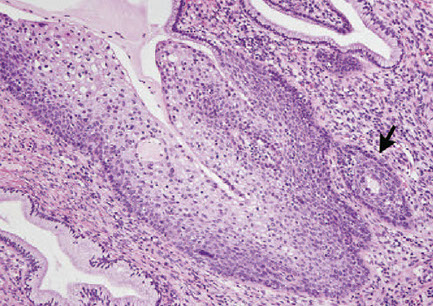

Sarcoma botyroides

Rare form of embryonal rhabdomyosarcoma, in kids or early adolescents

- Grape-like mass protruding from vagina

Micro: rhabdomyoblasts at different stages of maturation

- cambium layer (dense group of cancer cells) under cervical epithelium

- might not look atypical in kiddas